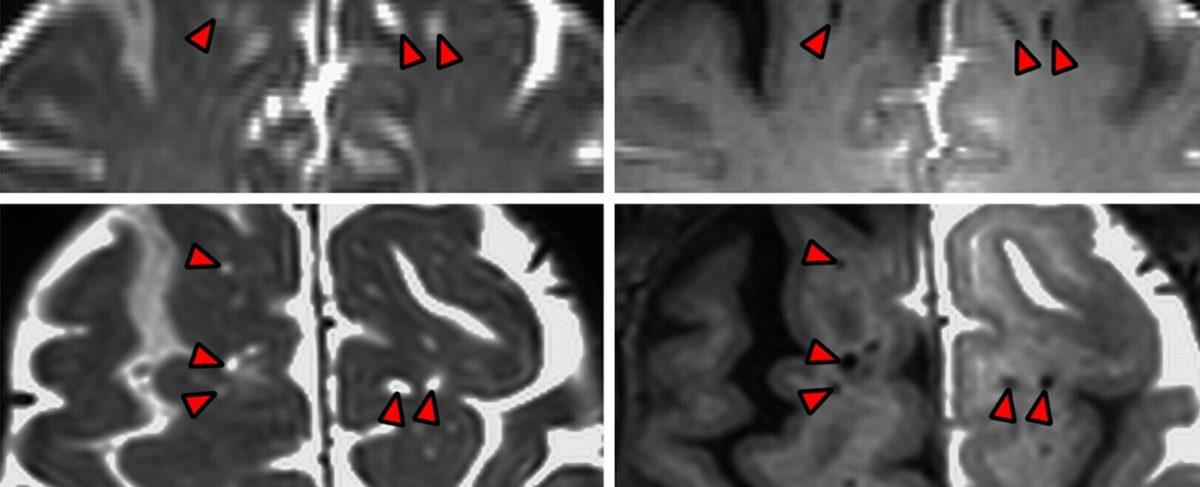

Beynimiz, çevresini saran beyin omurilik sıvısı ile çevrelenmiştir. Beyin omurilik sıvısı, beyni çevresel etkilerden korumanın yanı sıra, besinleri beynin içine aktarır. Buna paralel olarak beyinde biriken atıklar da yine beyin omurilik sıvısı ile dışarı atılır. Yapılan çalışma, bu karmaşık sürecin nasıl çalıştığını, atıkların beyin dışına nasıl gönderildiğinin görüntülenebilmesini sağladı. İşte yukarıdaki fotoğrafta kırmızı oklarla gösterilmiş noktalar, insan beyninin sıhhi tesisatı.

Araştırmaya liderlik yapan Nörolog Juan Piantino, bu araştırma için beyin ameliyatı geçirmek zorunda olan 5 hastayı bulduklarını anlattı. Bu hastaların beyin omurilik sıvılarını renklendiren uzmanlar, sonraki aşamada bu sıvının hareketini incelediler. İşte yapılan inceleme ve özel görüntüleme teknikleri, insan beyninin bu sıvıdaki besinleri rastgele almadığını, belirli yollar üzerinden aktarılan sıvının beyin dokusuna ulaştığını gözler önüne serdi. Atıklar da yine bu yollar üzerinden beyin dokusu dışına gönderiliyordu.